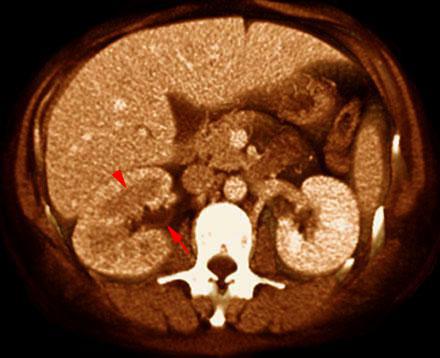

Pielonefritis aguda 1

VR seccional. Visión axial caudal. Riñón derecho aumentado de tamaño y con disminución de la contrastación. En valva anterior se aprecia un área moderadamente hipodensa (punta de flecha). Moderado engrosamiento del urotelio de la pelvis renal (flecha)